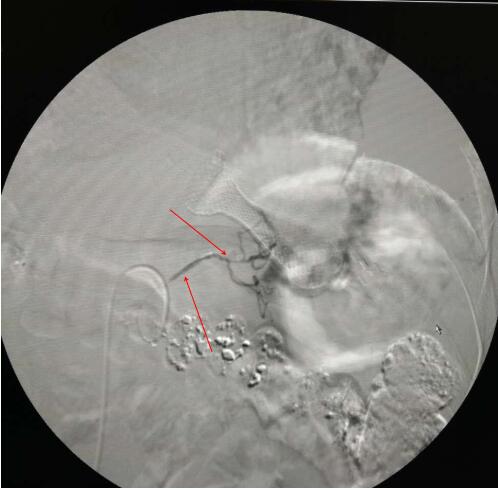

利用同轴微导管超选择肿瘤主要供血动脉

(图中箭头所指为肿瘤主要供血动脉)